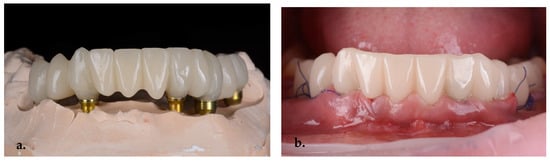

For the final restorations, monolithic zirconia was used for optimal biologic compatibility and superior strength (Figure 18a–f). The patient’s esthetics and function were fully restored. The intraoral pictures showed significant improvement in the micro esthetical characteristics. The gingival margins were levelled, and the teeth axes were corrected.

Figure 18.

Intraoral pictures of the result of monolithic zirconia-fixed partial dentures on teeth and implants: (a) upper incisors, (b) lower incisors, (c) right lateral view, (d) frontal occlusal view, (e) upper arch and (f) lower arch.